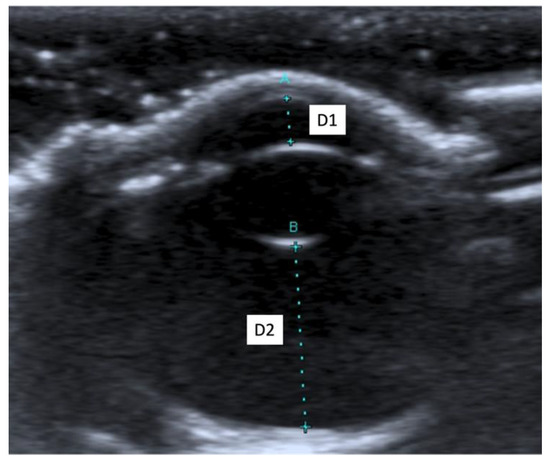

3.2. Ultrasound Biometric Measurements

| (a) | |||||||||||||||

| Both breeds | OS 1 (n 3 = 27) | OD 2 (n 3 = 27) | Mean OS 1 + Mean OD 2 | ||||||||||||

| D1 5 | D2 6 | D3 7 | D4 8 | D5 9 | D1 5 | D2 6 | D3 7 | D4 8 | D5 9 | D1 5 | D2 6 | D3 7 | D4 8 | D5 9 | |

| Mean (mm) | 1.68 | 7.41 | 4.29 | 15.09 | 18.01 | 1.66 | 7.48 | 4.32 | 15.16 | 18.07 | 1.67 | 7.44 | 4.30 | 15.12 | 18.04 |

| SD 4 (mm) | 0.16 | 0.18 | 0.11 | 0.44 | 0.49 | 0.16 | 0.20 | 0.17 | 0.37 | 0.49 | 0.12 | 0.17 | 0.12 | 0.37 | 0.43 |

| Median (mm) | 1.70 | 7.40 | 4.30 | 15.20 | 18.10 | 1.70 | 7.50 | 4.30 | 15.20 | 18.00 | 1.65 | 7.45 | 4.30 | 15.05 | 18.05 |

| Maximum (mm) | 2.10 | 7.70 | 4.50 | 15.80 | 18.80 | 1.90 | 7.80 | 4.70 | 15.90 | 18.90 | 1.95 | 7.75 | 4.55 | 15.80 | 18.85 |

| Minimum (mm) | 1.40 | 7.00 | 4.10 | 14.30 | 16.80 | 1.30 | 7.10 | 4.10 | 14.60 | 17.30 | 1.45 | 7.05 | 4.10 | 14.50 | 17.25 |